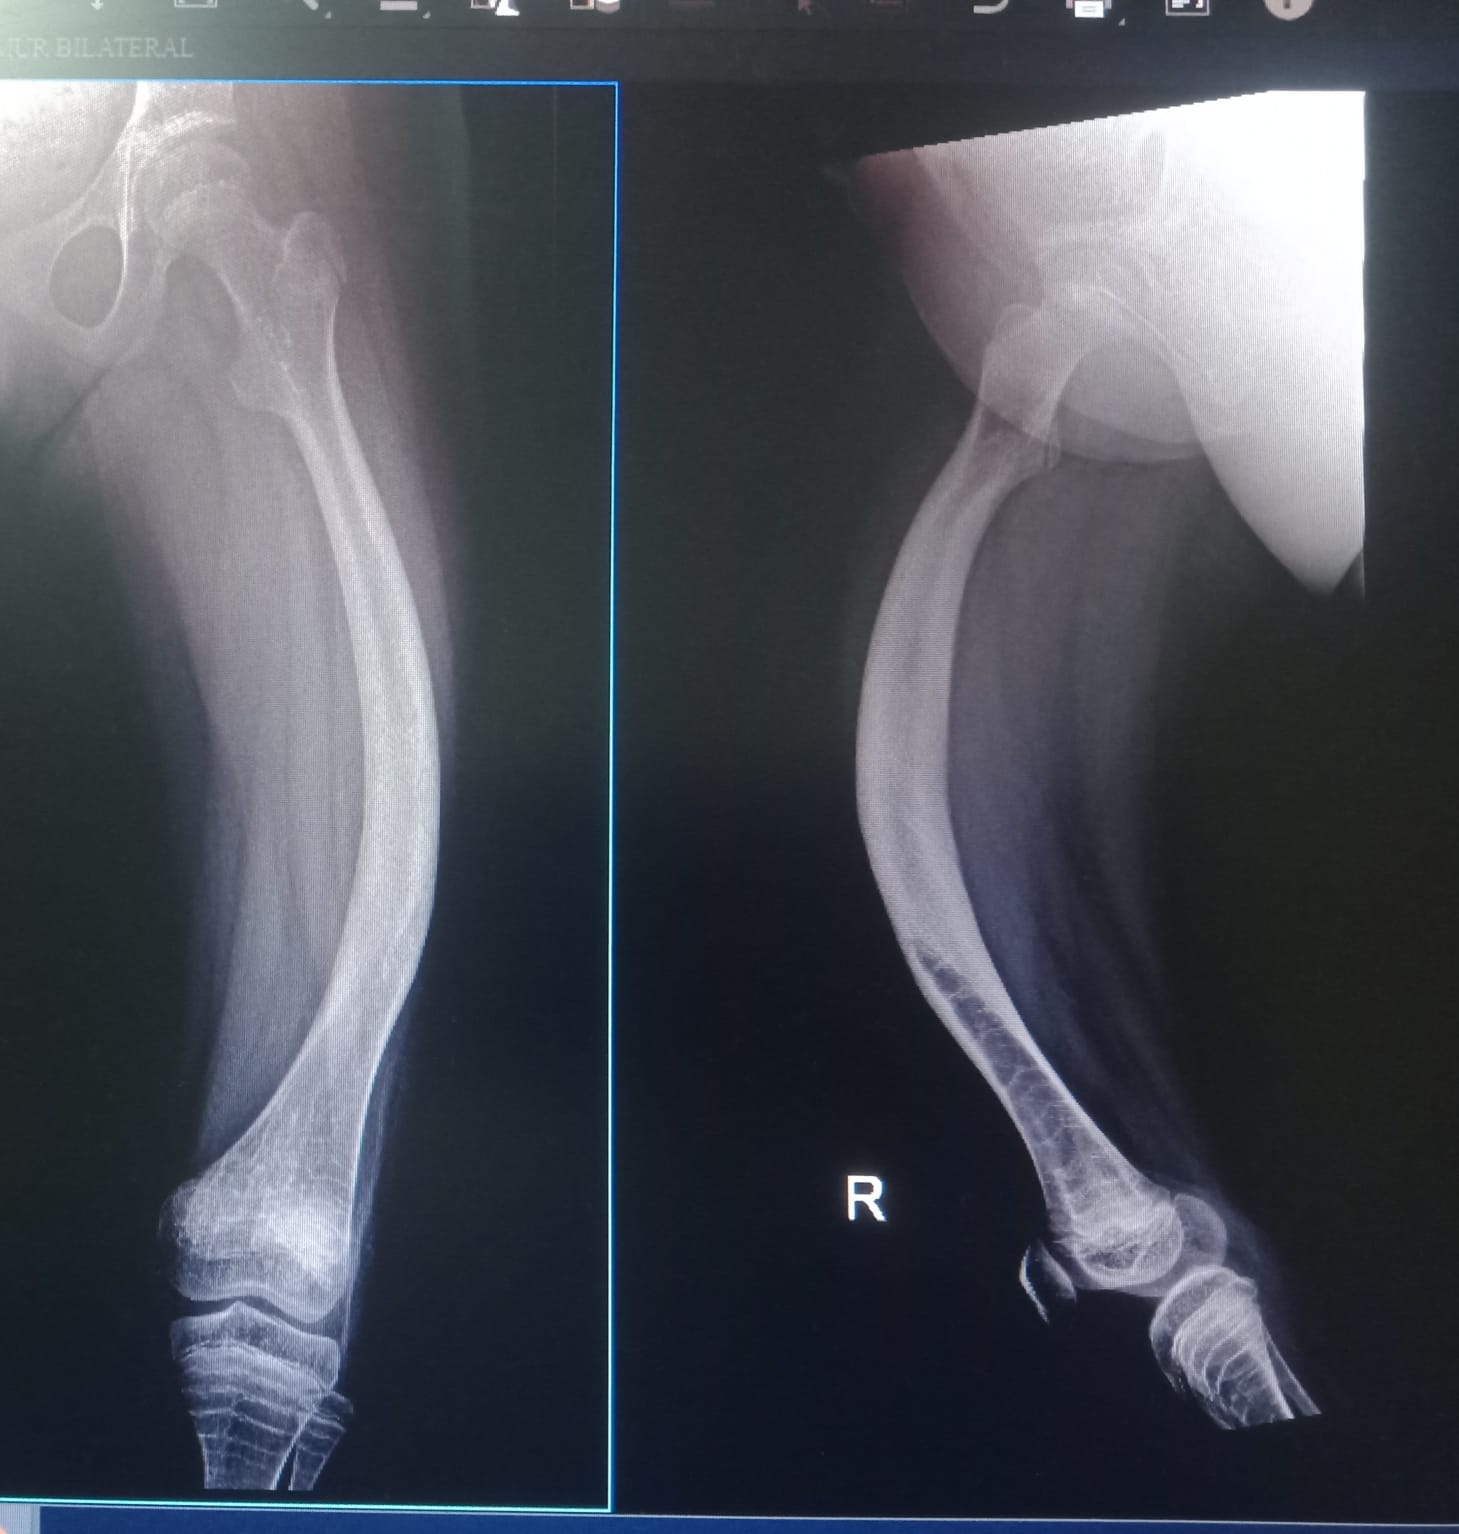

Di RSCM, Anza menjalani pemeriksaan rontgen dan pemeriksaan lainnya didapati bahwa kedua tulang kaki Anza bengkok dan rapuh. Ternyata Anza menderita penyakit langka yakni osteogenesis imperfecta tipe III.

“Dokter bilang tulang Anza sangat rapuh. Sehingga apabila terjatuh atau terbentur bisa langsung patah” ibu Anza.

Saat itu kaki Anza langsung dipasang gips agar rasa sakit yang Anza rasakan berkurang patahannya membaik. Setiap kali tulang kakinya patah, Anza selalu menjerit kesakitan saat kakinya tersentuh. Karena di Indonesia belum ada pen khusus osteogenesis, dokter menyarankan Anza untuk menjalani operasi pemasangan pen di Singapore.